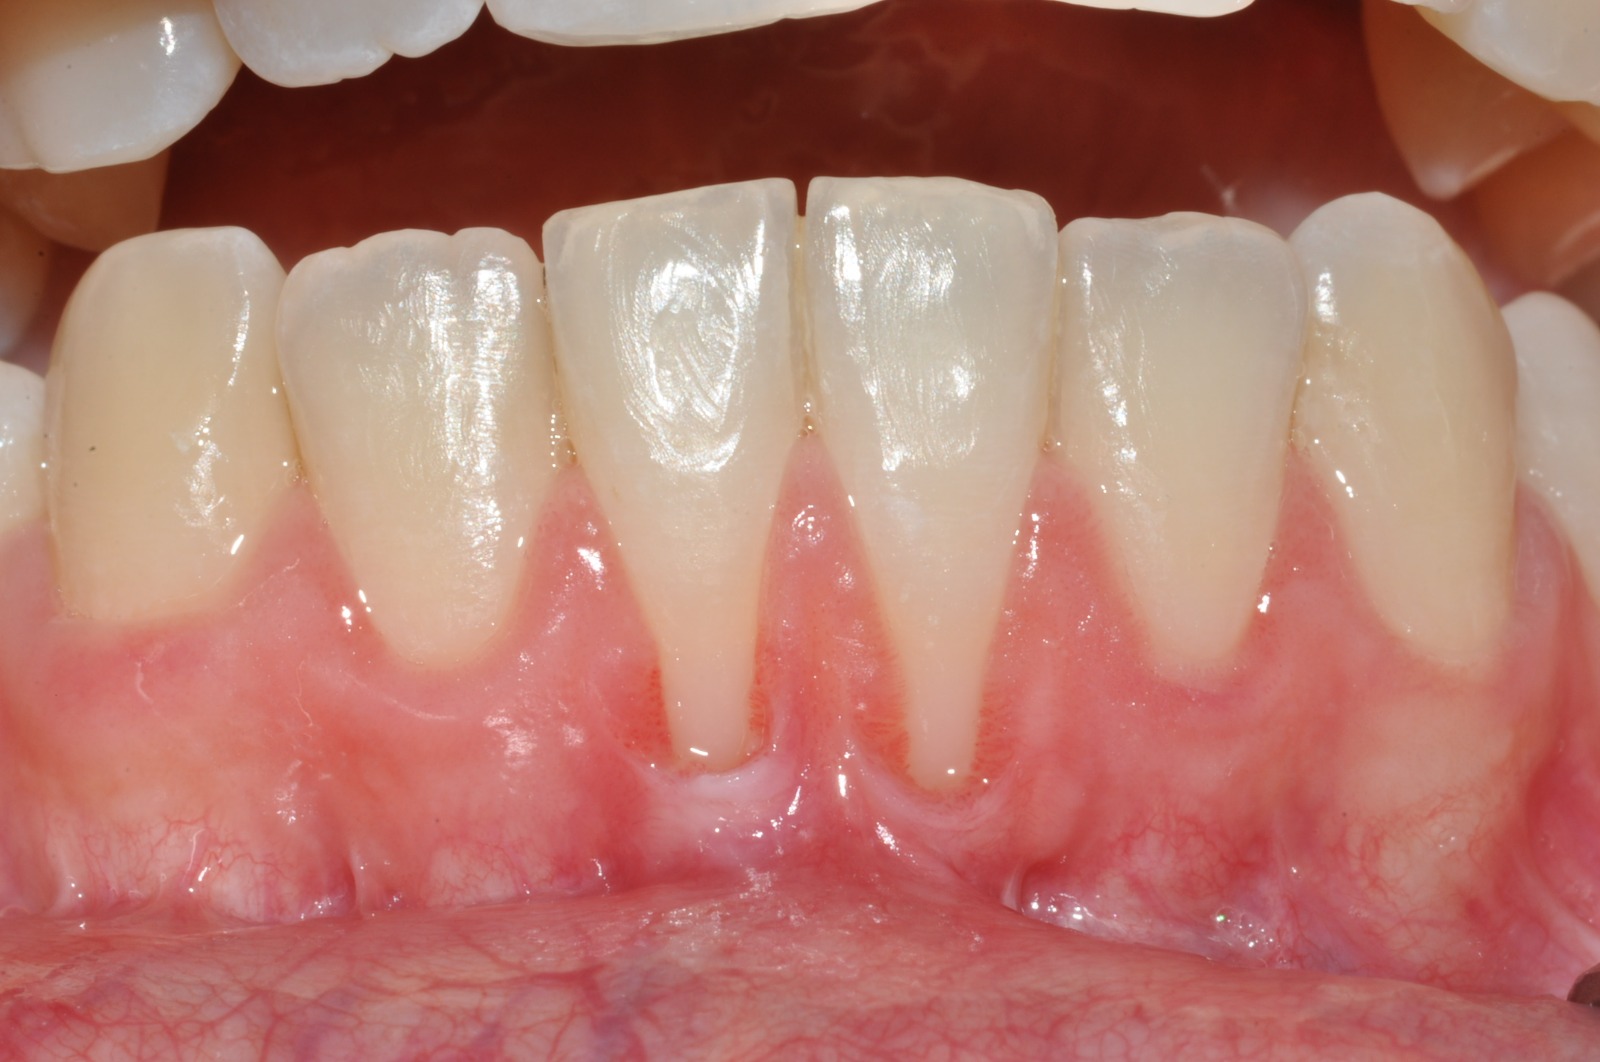

I colletti dentali scoperti e l’esposizione delle radici dei denti sono una conseguenza della recessione gengivale, che è quel fenomeno che si registra ogni qualvolta il tessuto gengivale migra dalla sua posizione fisiologica in direzione apicale, quindi verso la radice del dente; la recessione gengivale può essere di varia entità, e portare a conseguenze e fastidi più o meno gravi, quali sensibilità aumentata, maggior rischio di sviluppare carie nelle porzioni di dente scoperte in conseguenza alla recessione gengivale, oltre che alterazioni di tipo estetico.

- Denti scoperti o allungati, a causa di una maggior porzione di dente esposta, e quindi alterazione estetiche della bocca

- Hai notato che alcuni dei tuoi denti sembrano più lunghi rispetto a qualche anno fa? Questa sensazione di "denti allungati" non è solo un'impressione, ma un segnale che le tue gengive potrebbero essersi ritirate, esponendo una maggiore porzione di dente. Questo fenomeno non solo può causare sensibilità dentinale, ma può anche alterare l'aspetto estetico della tua bocca. Un sorriso in cui i denti sembrano eccessivamente lunghi può influire sulla fiducia in sé stessi, rendendo alcune persone più riluttanti a sorridere apertamente. Prendersi cura dei denti è fondamentale non solo per la salute dei denti, ma anche per mantenere un sorriso armonioso e piacevole.

- Presenza di spazi vuoti tra i denti e giunzione amelo-cementizia visibile (la linea che delimita la fine della corona del dente ricoperta da smalto e l’inizio della radice dello stesso ricoperta invece da cemento radicolare)

- È possibile che abbiate notato che di recente la giunzione amelo-cementizia è visibile (la linea che delimita la fine della corona del dente ricoperta da smalto e l’inizio della radice dello stesso ricoperta invece da cemento radicolare). Questo fenomeno è un segno normalmente di recensione gengivale, perché questa zona del dente in condizioni di salute risulta essere coperta dal margine gengivale.